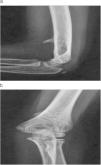

En la radiografía simple de codo se aprecia una apófisis ósea supracondílea con dirección anterior y medial en el lugar de la tumoración (figs. 1a y b).

Se diagnosticó de atrapamiento del nervio mediano entre la apófisis supracondílea y el ligamento de Struthers y se realizó neurólisis mediana y exostosectomía de la apófisis ósea. A un año de la cirugía, la recuperación es completa.